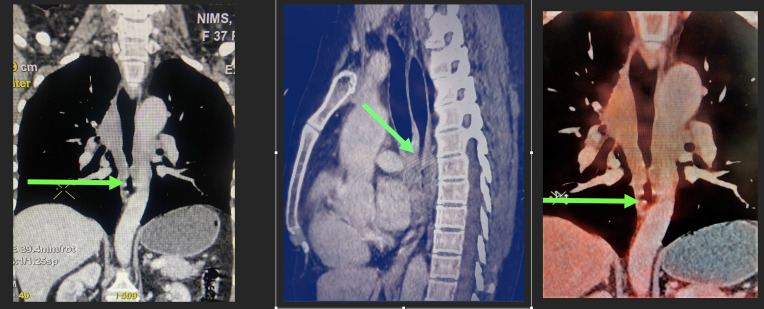

Immunoglobulin G4-related disease (IgG4-RD) coexisting with clinically apparent autoimmune diseases, such as rheumatoid arthritis (RA) or antiphospholipid syndrome (APS), is a rarely documented combination in the scientific literature. In this case-based review, we present 2 intriguing cases with preexisting autoimmune diseases, namely, RA and primary APS, who exhibited coexistent IgG4- related lesions at unusual sites. The first case pertains to a patient with known RA who presented with an encasing mass in the esophagus leading to stricture, with histopathological diagnosis of IgG4-RD.The second patient, diagnosed with primary APS, experienced breathlessness, and imaging revealed a right atrial mass. Histopathological examination of the mass confirmed IgG4-RD. Notably, both patients demonstrated significant clinical improvement upon initiation of steroid therapy. Rheumatoid arthritis patients commonly exhibit elevated levels of IgG4 in their sera; however, RA with coexisting IgG4-RD is rarely reported in the literature. Similarly, APS with IgG4-related lesions is exceedingly rare. Although there are few case reports and series on esophageal and cardiac IgG4-RD, the occurrence of such unusual location of IgG4-related lesions in the context of known autoimmunity is presented here for the first time.